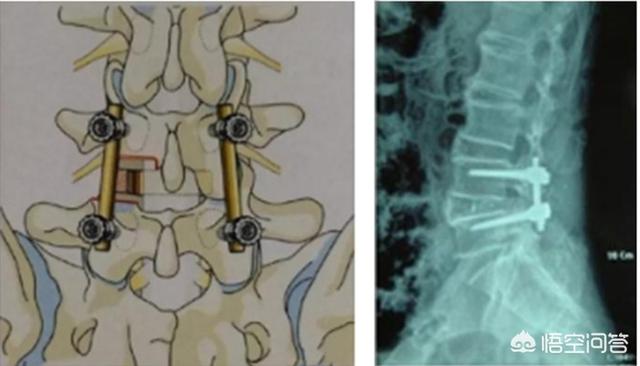

2.後方開放プレート除圧ペディキュラースクリュー内固定術。

通常、椎弓切除術で解決できない手術も、この手術で解決できる。

椎間板ヘルニアを摘出すると、椎骨間の安定性の一部が失われるため、腰痛を引き起こすだけでなく、腰の変性が促進される可能性があるからです。そこで、すでに腰が不安定な高齢の患者さんには、椎間板をすべて取り除き、癒合器具を装着して腰を内固定で固定する、1回きりの癒合手術が可能です。この手術のリスクは、椎間板の摘出だけよりも大きくなります。